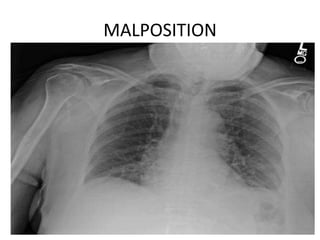

MALPOSITION